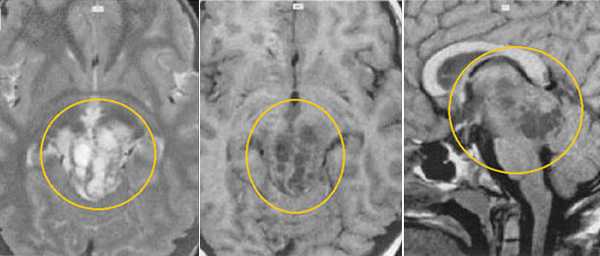

Пинеобластома. В режиме Т2 и Т1 выявляется опухоль задних отделов III желудочка мозга с развитием окклюзионной гидроцефалии. В строме опухоли небольшой участок подострого кровоизлияния. После в/в контрастирования опухоль интенсивно и достаточно гомогенно накапливает контрастирующее вещество.

Герминома пинеальной области. На Т2 ВИ опухоль имеет слабо гиперинтенсивный сигнал по сравнению с тканью мозга, тогда как на Т1 опухоль практически изоинтенсивна с мозгом. Желудочковая система гидроцефально расширена. III желудочек деформирован. Четверохолмная пластинка оттеснена кзади.

Герминома пинеальной области. Опухоль имеет гетерогенное строение с множеством мелких и крупных кист. Вокруг опухоли определяется перифокальный отек.